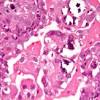

A New Treatment Fights Endometrial Cancer With Nanoparticles At the University of Iowa (UI) College of Pharmacy, researchers are working to improve treatment methods for a particularly aggressive form of endometrial cancer.